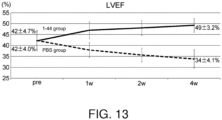

- Echocardiography was performed prior to dosing, and at 4 and 6 weeks after dosing; and left ventricular end-diastolic diameter (LVDd), left ventricular end-systolic diameter (LVDs), and left ventricular ejection fraction (LVEF) were measured and calculated to perform a cardiac function assessment.

- Echocardiography was performed prior to dosing, at 4 weeks after dosing, and every 2 weeks thereafter to measure LVEF.

- the LVEF of the HMGB1 peptide (1-44) group remained significantly higher than that of the PBS group until 6 weeks after administration ( FIG. 9 ).

- Echocardiography was performed at 1, 2, and 4 weeks after dosing, and the left ventricular end-diastolic diameter (LVDd), left ventricular end-systolic diameter (LVDs), and left ventricular ejection fraction (LVEF) were measured and calculated to perform a cardiac function assessment.

- Cardiac function assessment at 4 weeks after dosing showed significantly higher levels of LVEF in the HMGB1 peptide (1-44) group compared to the PBS group ( FIG. 11 ).

- the PBS group showed a decrease in LVEF over time after dosing

- the HMGB1 peptide (1-44) group showed an increase in LVEF over time up to 4 weeks after dosing, with an average improvement in LVEF of about 7% with respect to before the dosing ( FIG. 13 ).